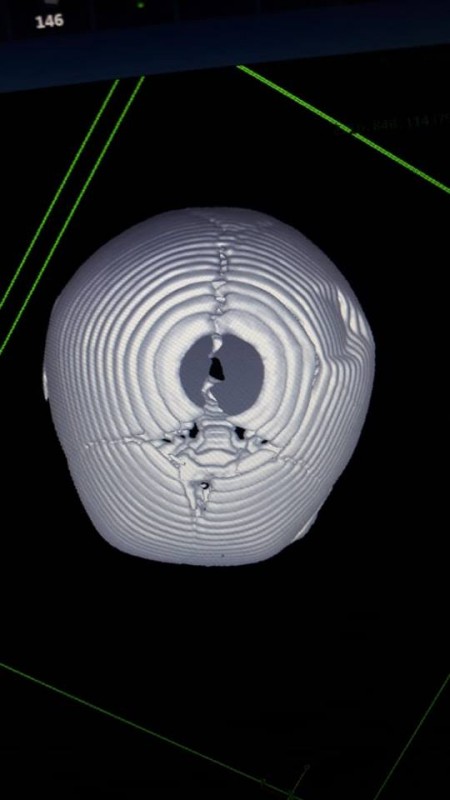

Девочка поступила в приемный покой детской больницы 25 июня с диагнозом "закрытая черепно-мозговая травма, вдавленный перелом теменной кости справа, ушиб головного мозга, анемия 1-й степени".

"В течение 30 минут врачи детской больницы проводили операцию по наложению фрезевого отверстия в область свода черепа. Оперировали ребенка Ербол Кенжевалов и Казбек Шукиров, анестезиолог - Казбек Келеманов. К счастью, операция прошла успешно. На данный момент ребенок чувствует себя хорошо, получает лечение", - написал Сарсенбаев.

Фото: facebook.com/azamat.sarsenbaev